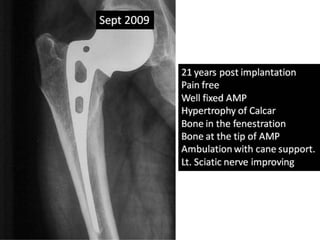

• Removal of Solution hip in Sept 2009.

Case summary •Persistent pain in hip and knee since revision. • Hip ultra-sonography in April 2009 – small pocket – aspiration negative. • No relief with antibiotics. • Removal of Solution hip in Sept 2009.

Case summary •Walking with stick. • Sciatic nerve is improving with active toes and ankle dorsiflexion. • Main complaint was limitation of knee movement, which is from 0 – 90 degree lt. • This is due to repeated surgery, muscle scaring and adherence to bone. • X-ray knee joint was normal